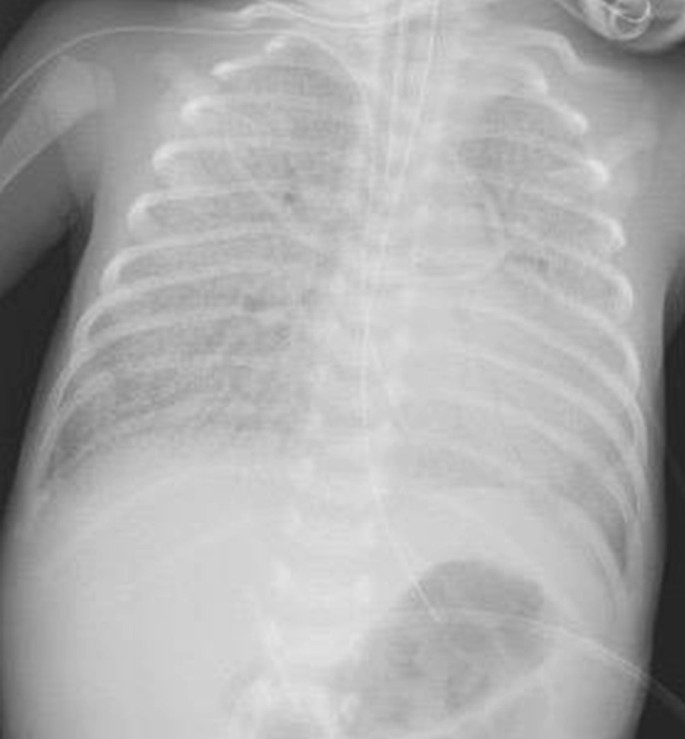

An immediate chest X-ray showed homogenous opacity of both lung fields disproportionate to his gestation (Fig. 1). The baby was initially managed by low flow nasal cannula which was replaced by high flow nasal cannula (HFNC) then NCPAP then the baby was intubated and connected to A/C mode of conventional ventilator, to end up on high frequency oscillation ventilation (HFOV) by the 3rd day of life due to the worsening of the respiratory distress, frequent desaturations and the chest X-ray which showed severe hyaline membrane disease (Fig. 2).

After few days of starting this treatment, the baby started to show marginal improvement and we were able to gradually shift him from HFOV to A/C mode of conventional ventilation and then he was shifted to HFNC on day 107 of life guided by blood gases and the clinical condition of the baby. Chest X-ray also showed a remarkable improvement (Fig. 3).